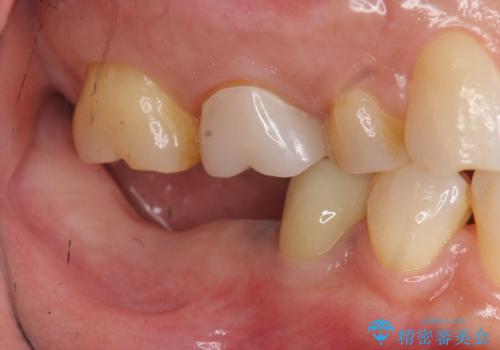

ブリッジを支える歯が割れてしまい、抜歯が必要であることと、骨の大きな吸収が見られました。

インプラント治療を行うにあたり周囲に骨を造成することで安定して噛める環境の整備を計画します。